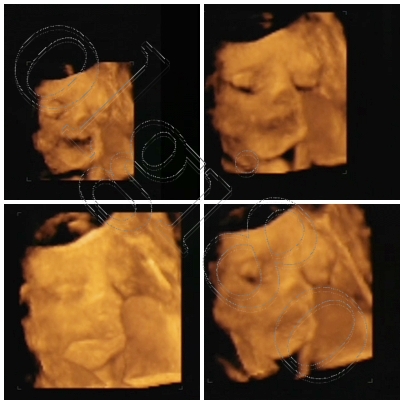

Kép

Leo, szuperek a képek! Nagyon édes! és már szopja az ujját!! :lol: :lol: